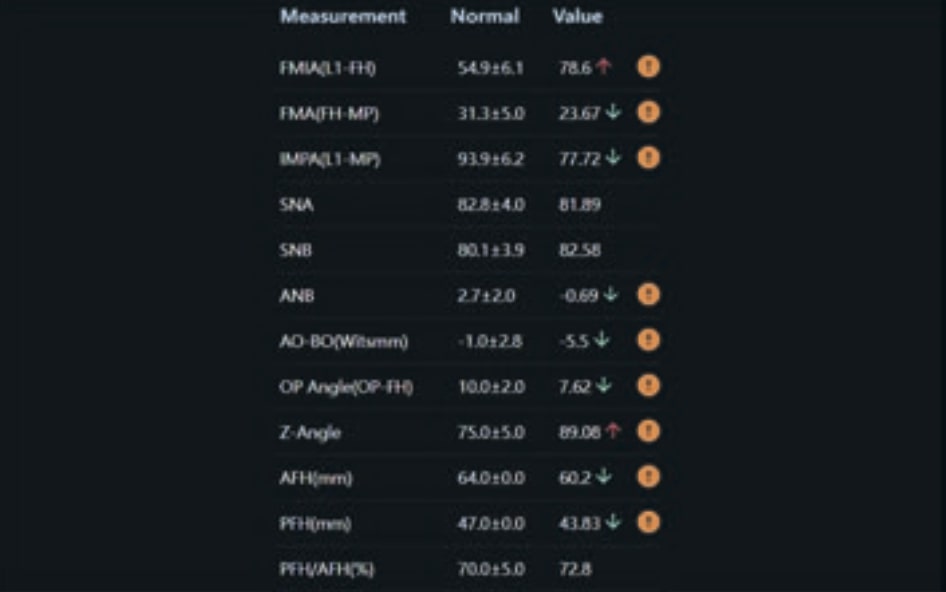

Clinical examination and diagnosis

- Patient Age: 19 years old

- Skeletal class III

- Dental Class III, 2 mm deviation of the lower midline to the left. 33 and 43 out of the arch and the cortical bone.

- Crossbite of 33.

- No functional issues

- Patient Motivation: General Review

- Soft Tissue Analysis: Jaw protrusion